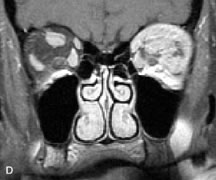

Pleomorphic adenomas demonstrate long T1 and T2 signal characteristics. They may show heterogeneity on T2-weighted images74 and moderate to marked enhancement with contrast.75 Signal characteristics of adenoid cystic carcinoma include hypointensity to fat on T1-weighted images, hyperintensity to fat with increased T2 weighting, and isointensity to fat on proton density-weighted studies (Fig. 23).31,75 Secondary bony alterations of the lacrimal fossa associated with lacrimal gland tumors, such as remodeling (benign mixed tumor) or destruction (adenoid cystic carcinoma), are seen indirectly on MR images; however, bone windows on CT scans provide better delineation of these changes. In contrast to the round or globular appearance of benign or malignant epithelial tumors of the lacrimal gland, lymphoproliferative tumors usually appear to be molding or draping onto the globe and the surrounding bony orbit.

Fig. 23. A. T2-weighted and (B and C) postcontrast fat-suppressed T1-weighted MR scans demonstrate an infiltrative lacrimal region mass than invades the lateral rectus muscle (arrows). This highly cellular lesion is seen to have a very hypointense appearance on the T2-weighted scan.